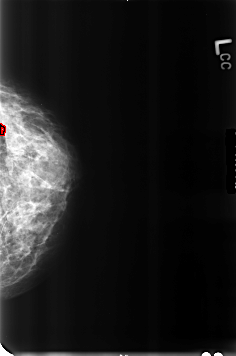

B_3231_1.RIGHT_CC

FILE: B_3231_1.LEFT_CC.OVERLAY

TOTAL_ABNORMALITIES 1

ABNORMALITY 1

LESION_TYPE CALCIFICATION TYPE PUNCTATE DISTRIBUTION N/A

ASSESSMENT 2

SUBTLETY 4

PATHOLOGY BENIGN_WITHOUT_CALLBACK

TOTAL_OUTLINES 1

BOUNDARY